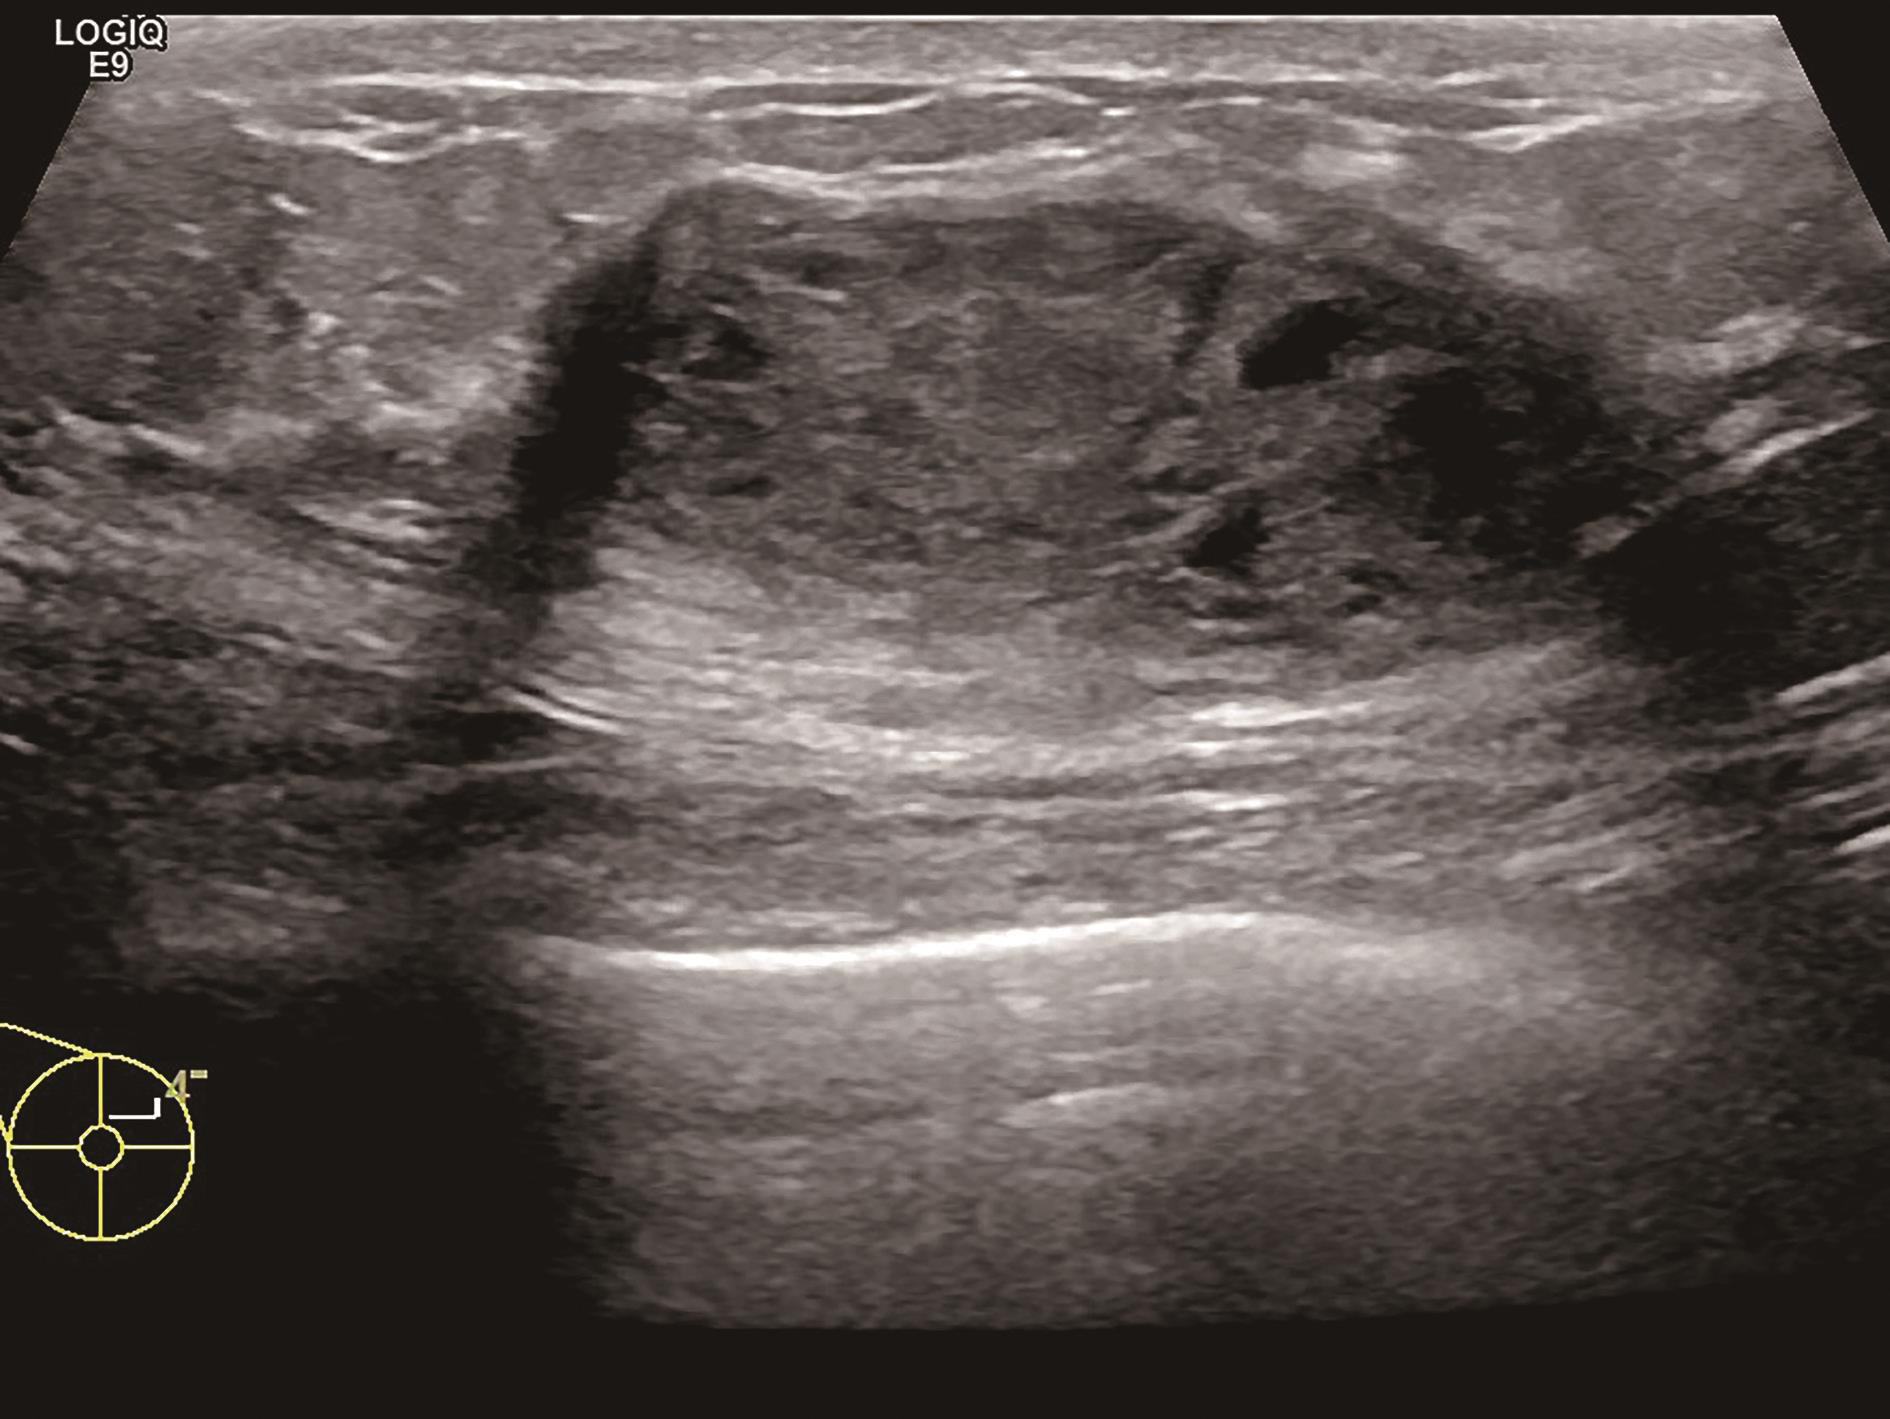

5.乳腺造影增强模式受多种情况影响,与病灶的发展阶段、分化程度、乳腺是否处于增殖期或哺乳期都有关系。如乳腺恶性肿瘤在其发展过程中会经历少血管期、富血管期(图2-2-11),尤其是当肿瘤还较小时,可能新生血管尚未形成,超声造影可表现出等增强甚至低增强,而在富血管期可表现出典型的快进高增强,而有出血坏死时可表现出无增强。同时,在同一非均质性病灶内,不同部位、不同回声类型及不同彩色血流表现的切面,造影也可表现出不一样的增强模式,所以拥有扎实的乳腺普通灰阶超声诊断基础是进行乳腺超声造影的前提。尽管乳腺超声造影表现复杂且多种多样,但基于6类乳腺超声造影良恶性预测模型(详见第三章第三节)进行判读可以解决大多数临床问题。